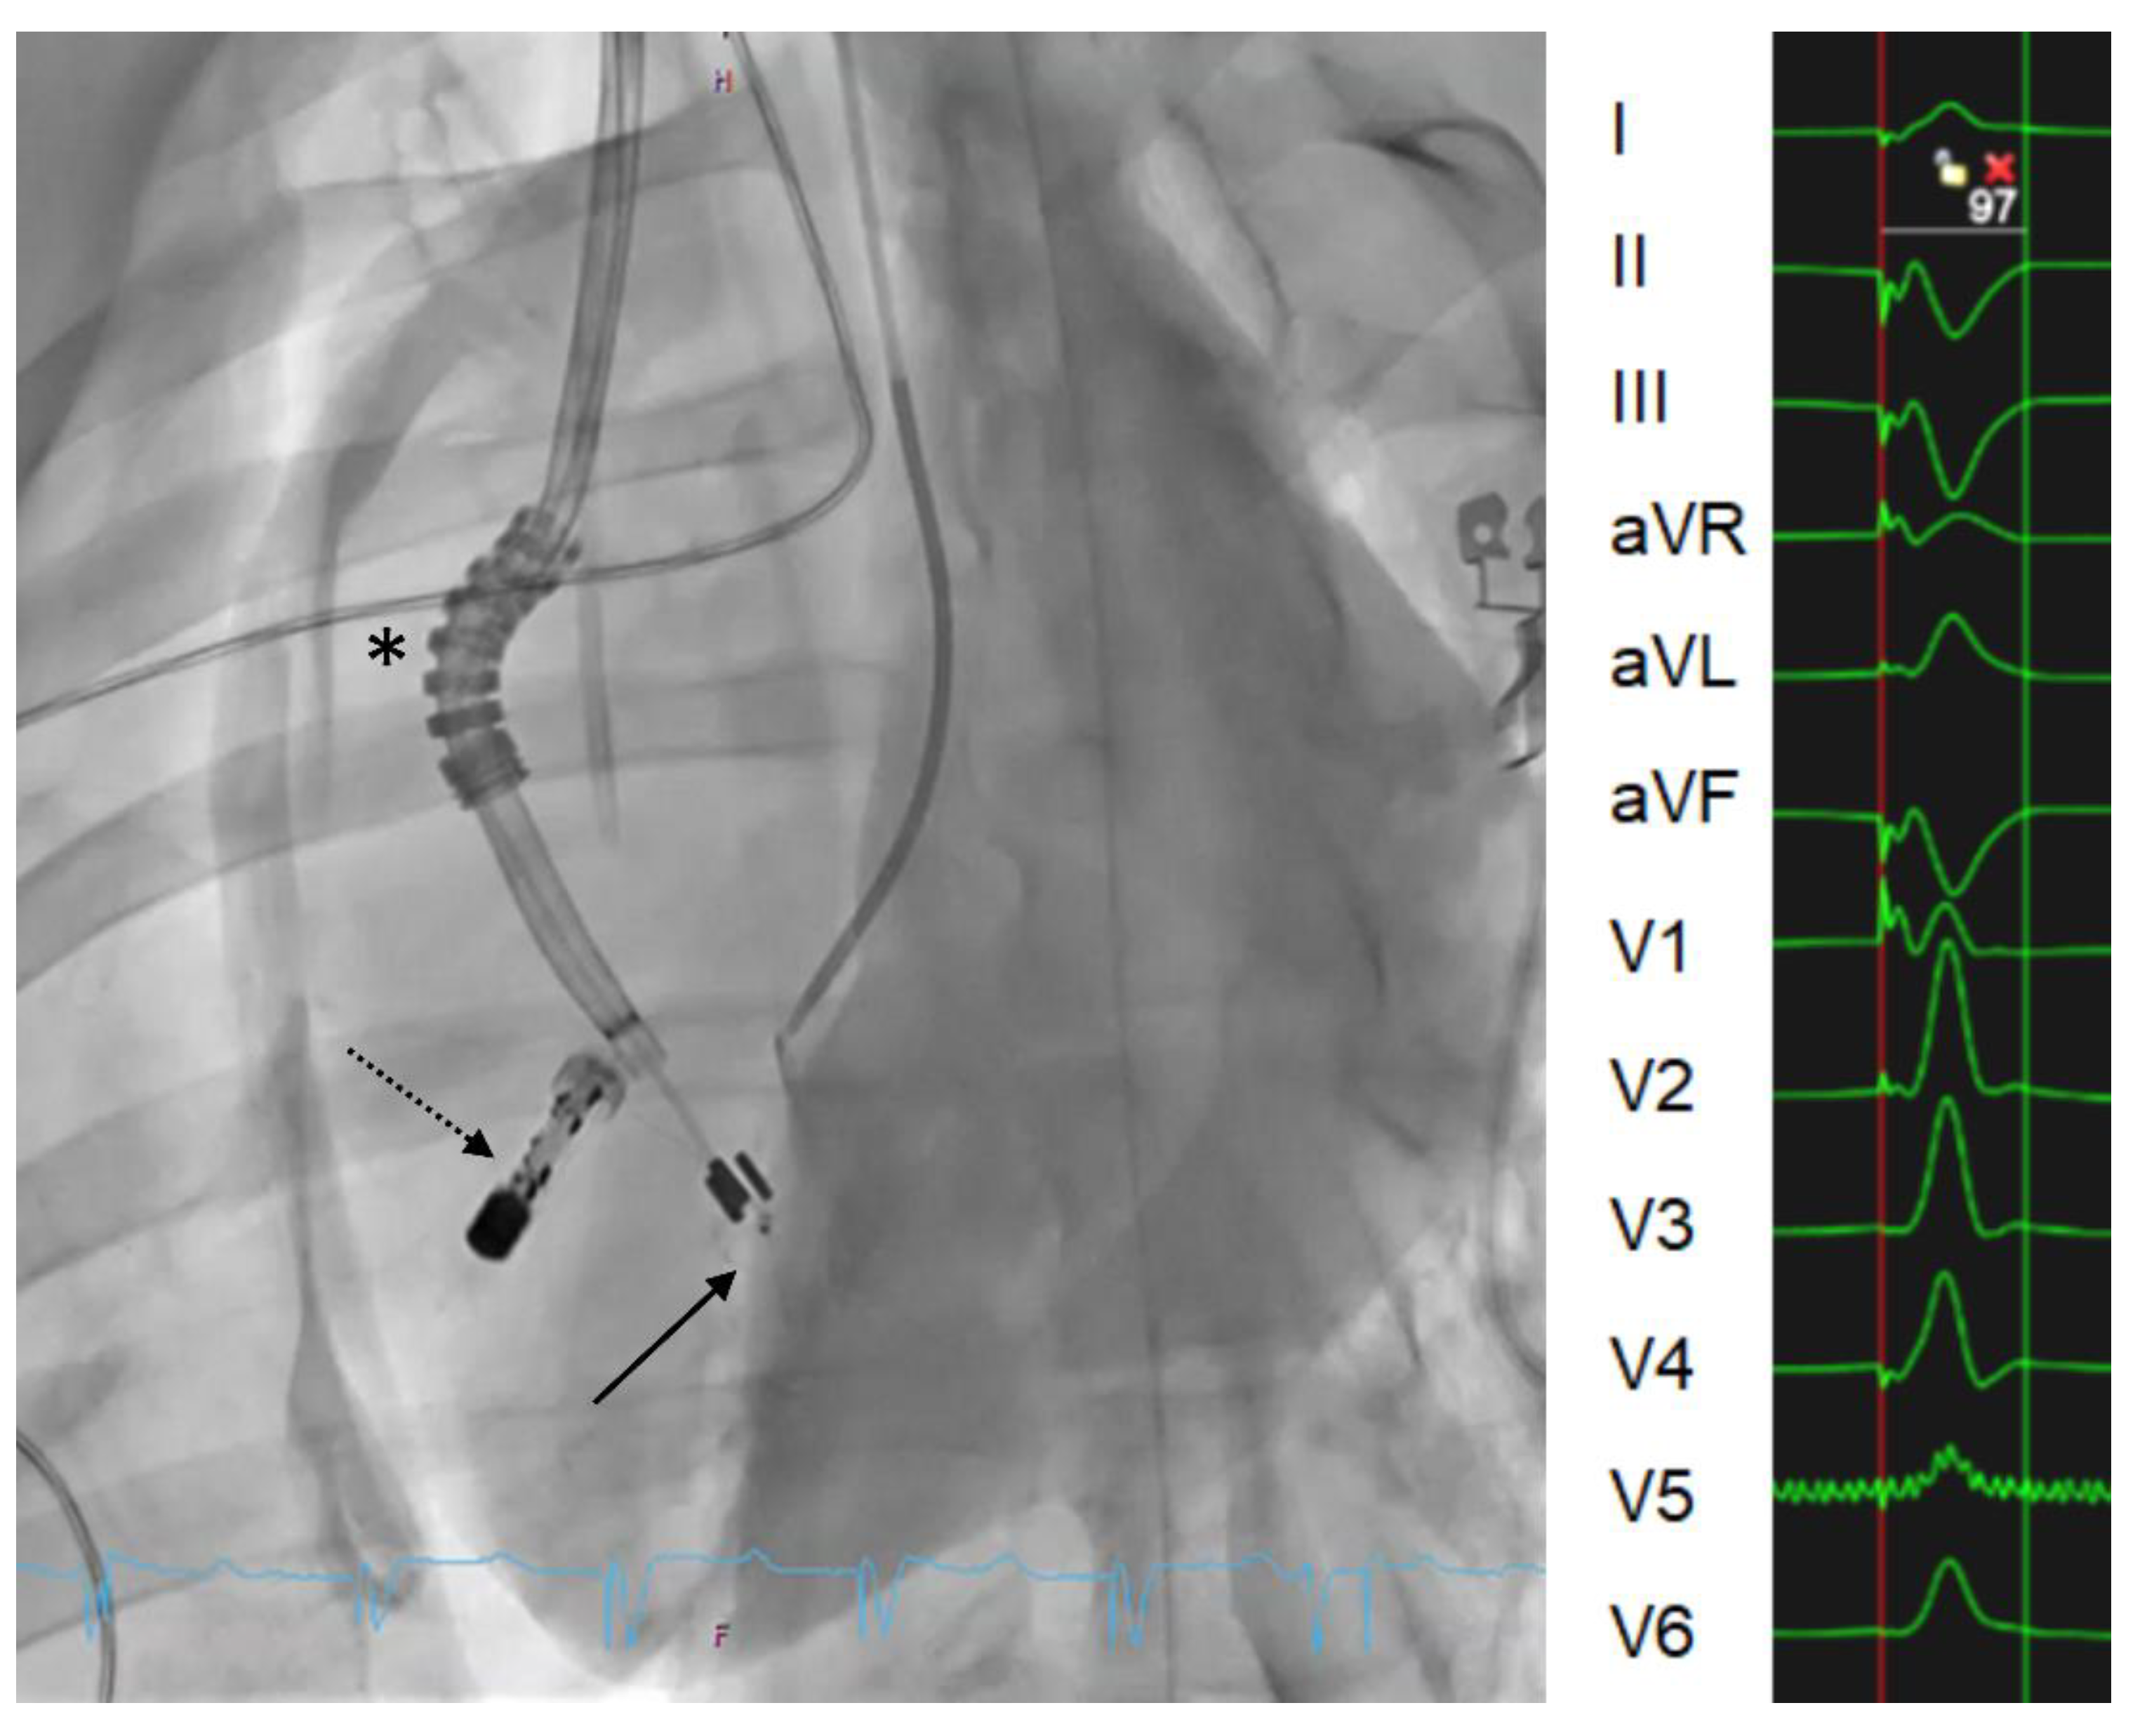

3.5. LBBAP Lead Implantation Technique